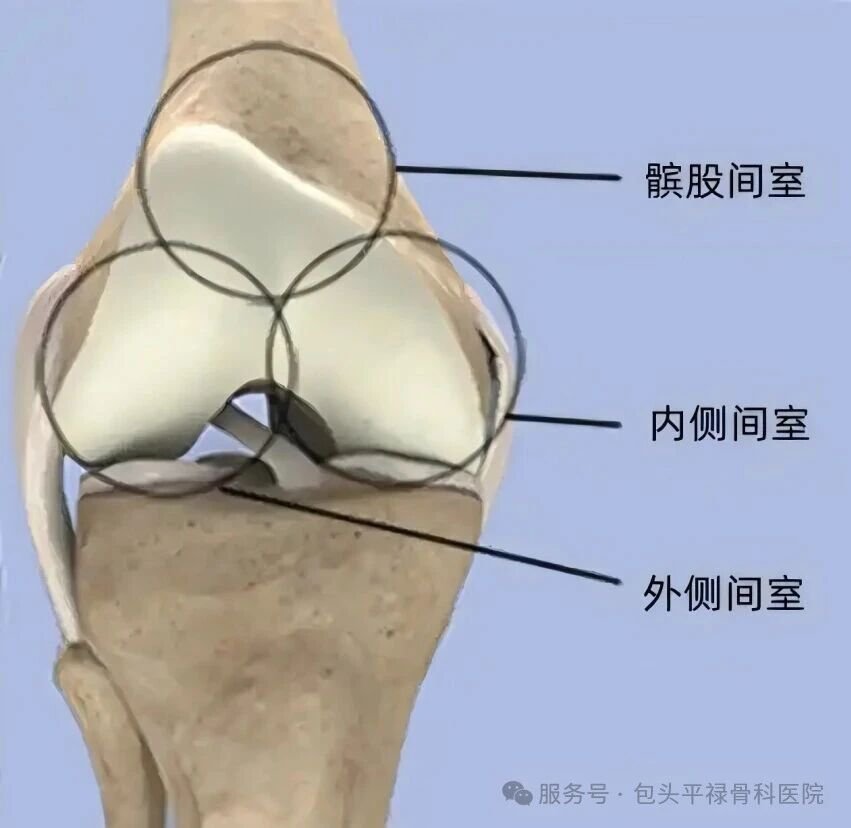

我们可以把膝关节想象成有三个“房间”的套房:

内侧间室(膝盖内侧)

外侧间室(膝盖外侧)

髌股间室(膝盖骨与股骨之间)

大多数的早期至中期膝关节炎,并不是所有“房间”都坏了,往往只是其中一个“房间”磨损严重(内侧间室最常见),而其他两个房间及关节的主要韧带仍然是健康的。

膝关节单髁置换术相当于“局部翻新”,就是只置换“坏掉房间”的磨损表面,仅将受损的软骨和部分骨质去除,替换为人工假体,而完好的软骨、交叉韧带及其他结构都得以最大程度的保留。